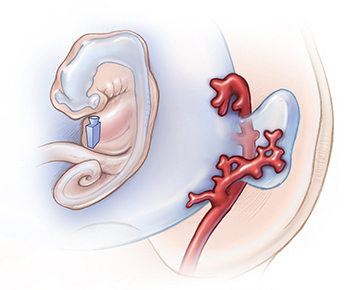

Lydia is an Associate Professor with a joint appointment in the Departments of Radiology and Art as Applied to Medicine. Her funded project entitled, Communicating Comparative Embryonic Arterial Development: An Interactive 3D Educational Tool Depicting Zebrafish and Human Ocular Arteries, seeks to visualize the development of major intracranial and ocular arteries by creating a comparative 3D educational tool that integrates human serial section data and zebrafish confocal microscopy data (Fig. 1). Developing this dynamic visualization will build on Lydia’s prior neurovascular embryology work (Fig. 2) 1-4 and experience illustrating, animating, and researching neurovascular anatomy 5-8.